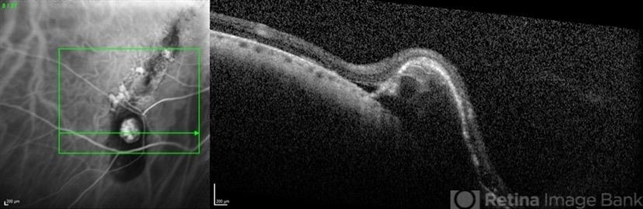

- tilted disc, atrophic pigment epithelium, polypoidal choroidal vasculopathy (PCV), optical coherence tomography (OCT), indocyanine green (ICG) angiography

- Coupled OCT B-scan and ICG angiography of an 81-year-old woman with a tilted disc syndrome complicated with RPE atrophy and polypoidal choroidal vasculopathy.